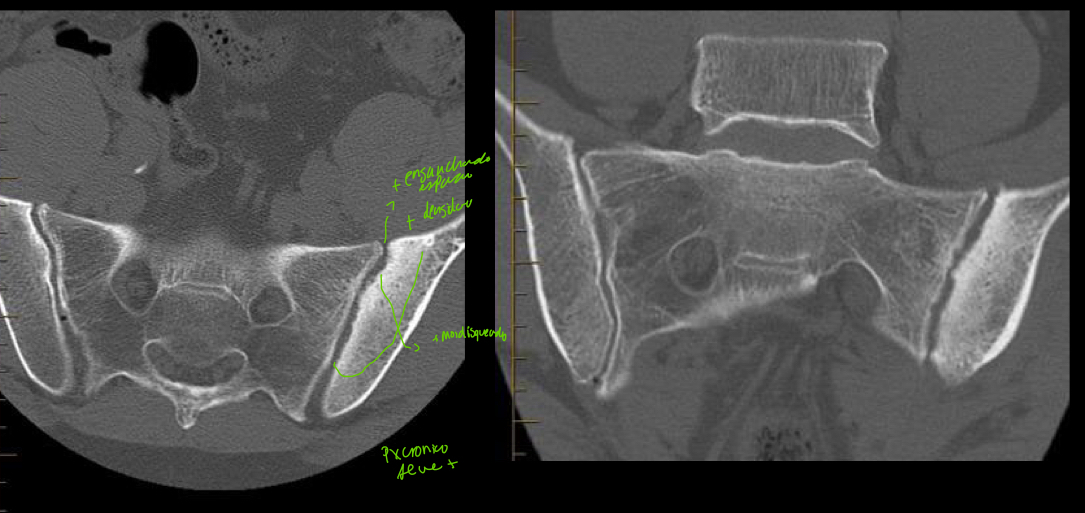

q se ve en rx y tc de sacroileitis?

A

poca sensibilidad

- Util en proceso cronico

- Esclerosis sacroiliaca : radiopacidad, se forma hueso

- Irregularidad y ensanchamiento

Que tiene

• ensanchamiento

• Mas densidad

• Mas mordisqueado

• En px cronico se ve mas